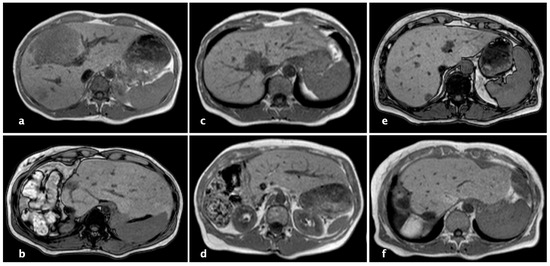

2.3. Technique of rALPPS

| FLV; mean, mL (SD) | |

| 1. Operation | 380.9 (138.1) |

| 2. Operation | 529.8 (163.0) |

| Hypertrophy; mean %, (SD) | 41.9 (13.2) |